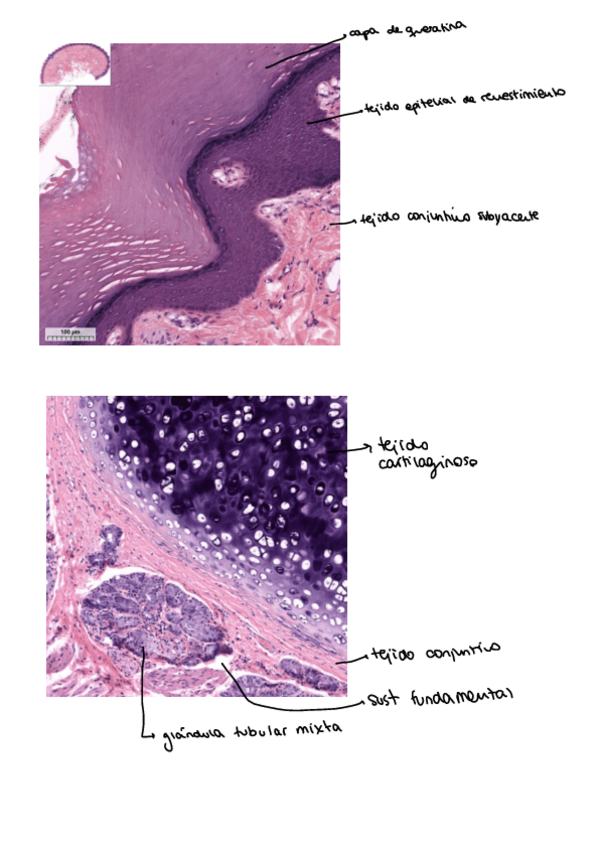

He publicado nuevos apuntes de 1º Anatomía e Histología Humanas: aparato-repiratorio.pdf

2 páginas

He publicado nuevos apuntes de 1º Anatomía e Histología Humanas: Tejido-epitelial.pdf

5 páginas

He publicado nuevos apuntes de 1º Anatomía e Histología Humanas: practicas-histologia.pdf

6 páginas